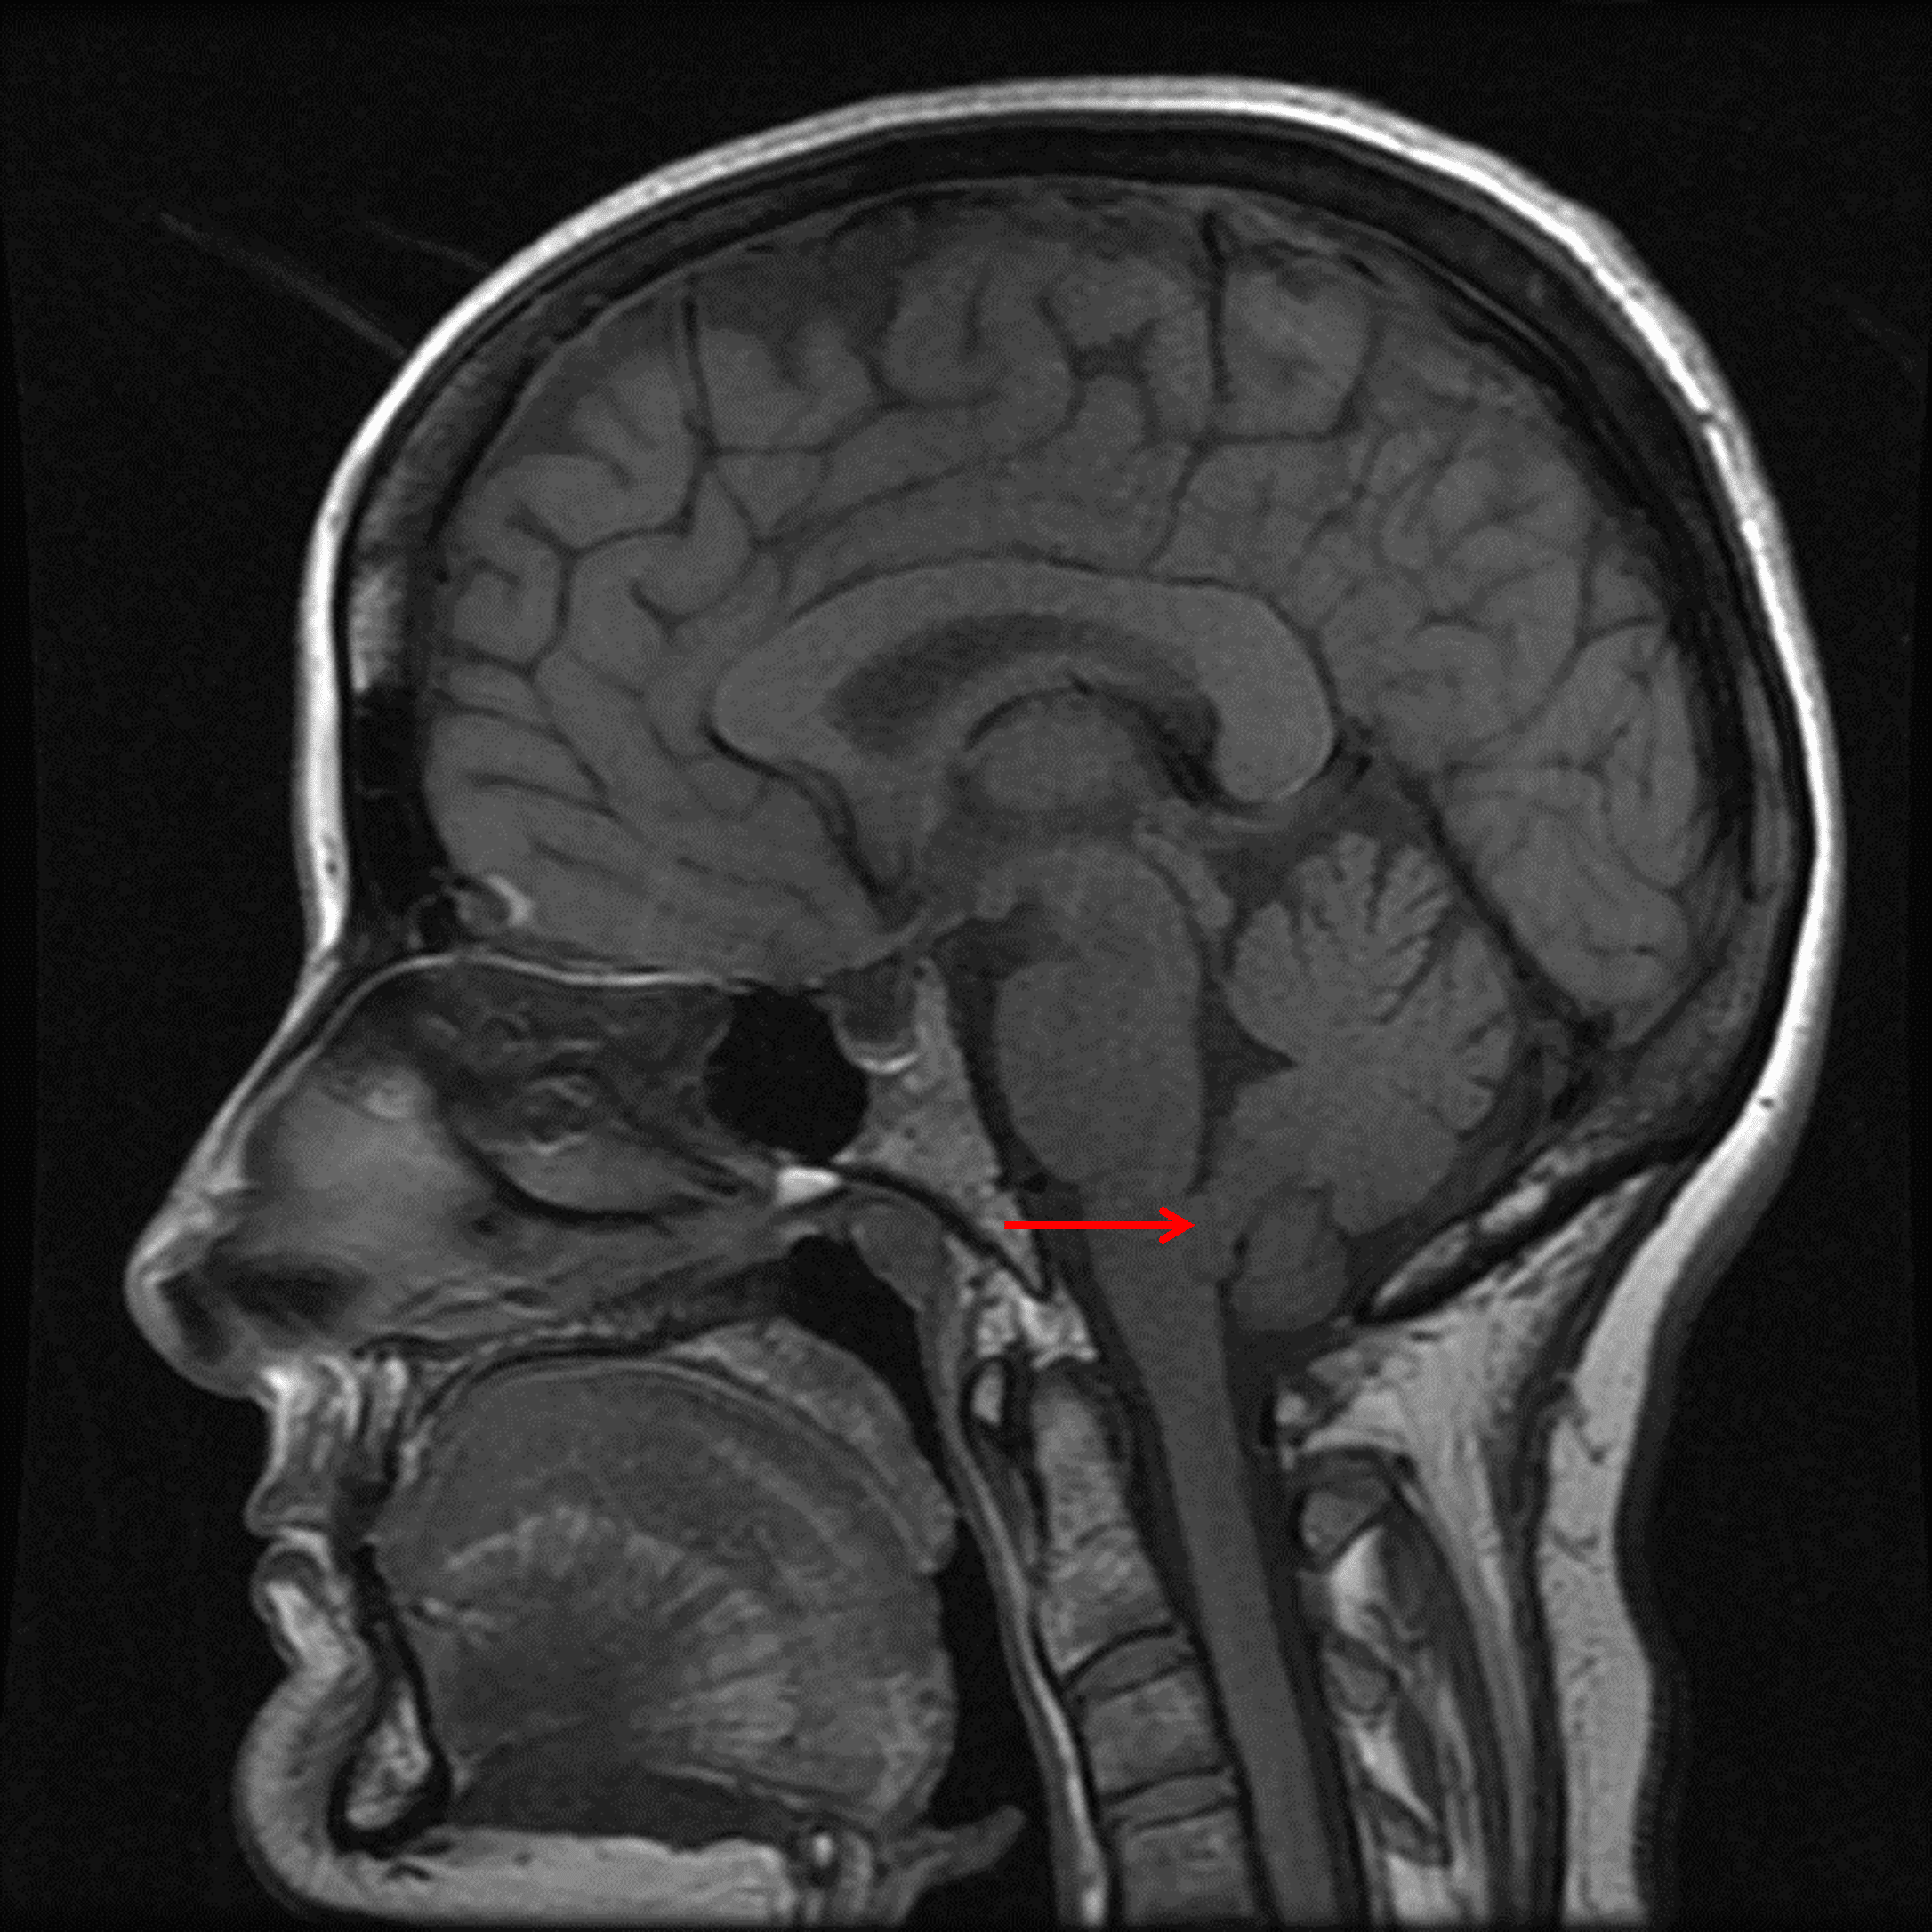

T1 isointense mass in the inferior aspect of the fourth ventricle (red arrow).